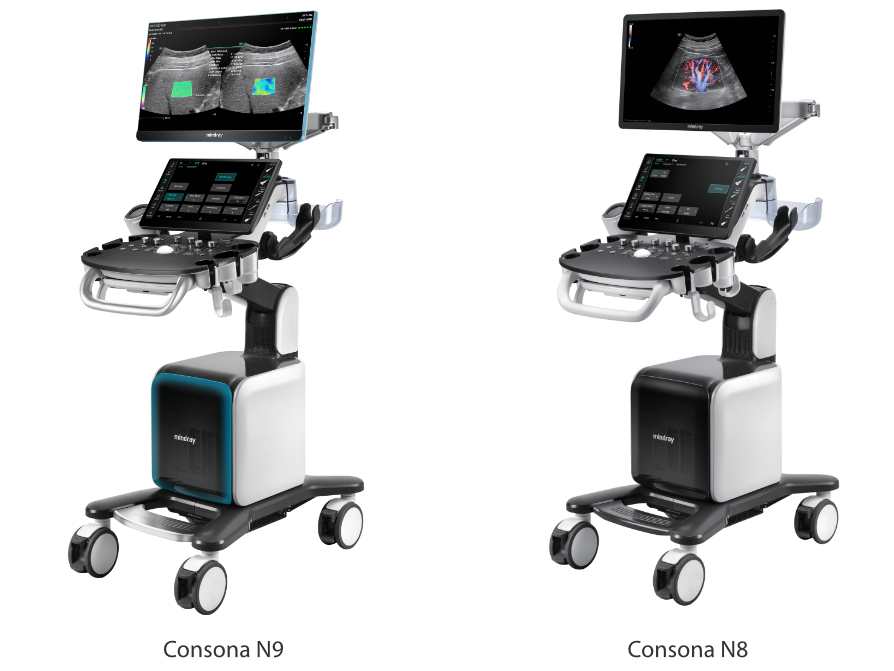

Concrete to Resonate

Stworzona specjalnie dla U?ytkownikÃģw z zakresu podstawowej opieki zdrowotnej, Consona wykorzystuje nowe rozwi?zania, ktÃģre efektywnie pomog? wykona? bez problemu diagnostyk? u rÃģ?nych pacjentÃģw.

Bez wzgl?du na to, czy pracujesz w szpitalu, przychodni, czy u?ywasz ultrasonografu do badaÅ ogÃģlnych, w opiece zdrowotnej kobiet lub w badaniach sercowo-naczyniowych, w serii Consona znajdziesz bardzo pot??ne narz?dzia, aby utrzyma? si? w czo?Ãģwce.

G?owice